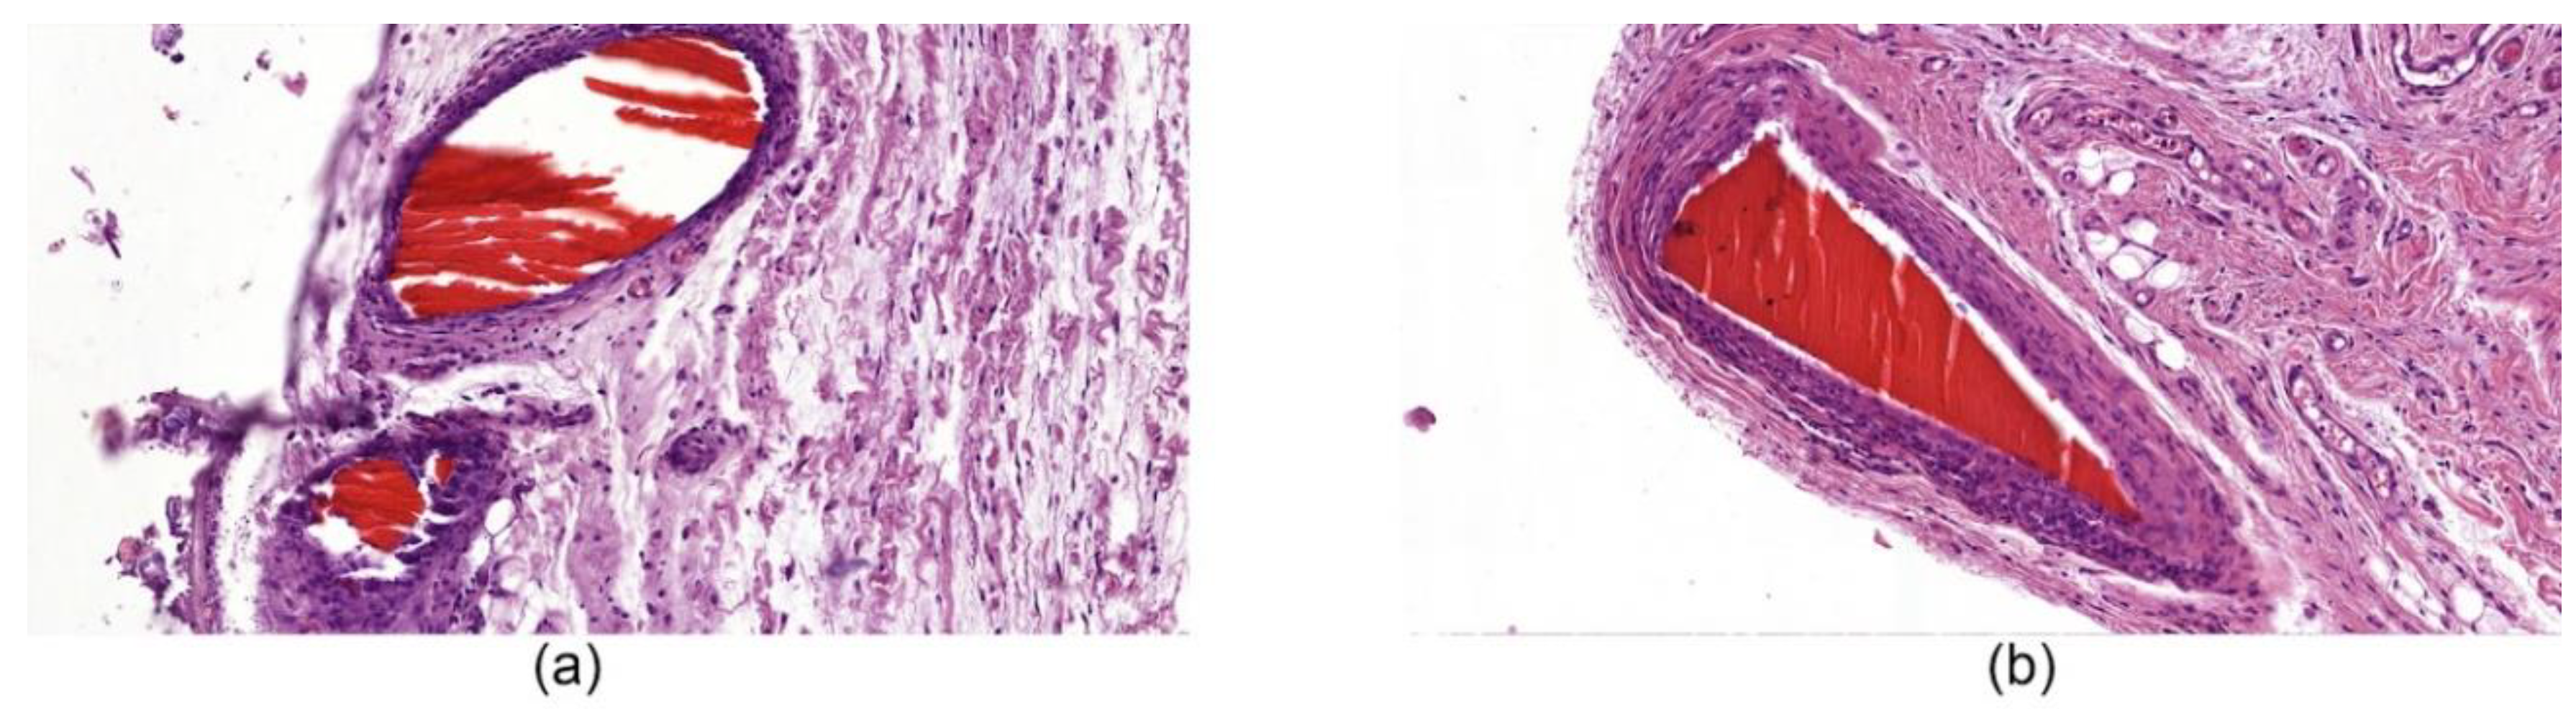

In the biopsy samples of the ChNF-chitosan filaments (0.5% of chitin) used in subfascial implantation, we observed a circle of coarse, fibrous connective tissue containing numerous fibroblasts with large bright oval-shaped nuclei. It was formed around the material in 14 days after beginning of the experiment (Figure 7a). In addition, focal lymphomacrophagous infiltration with an admixture of neutrophilic leukocytes (1–3 in the field of view, magnification 400×) and foreign body giant cells (1–2 in the field of view, magnification 400×) were found. On the 91st day of observation (Figure 7b), no signs of fiber resorption were observed. A narrow rim of scar tissue with small foci of lymphomacrophagous infiltration and an admixture of single neutrophilic leukocytes were present in the field of view (magnification 400×) around the fibers.

Figure 7. Histological microphotographs of biopsy samples of [chitosan + 0.5% ChNF] fibers, magnification 50×. (a) subfascial implantation, day 14; (b) subfascial implantation, day 91.